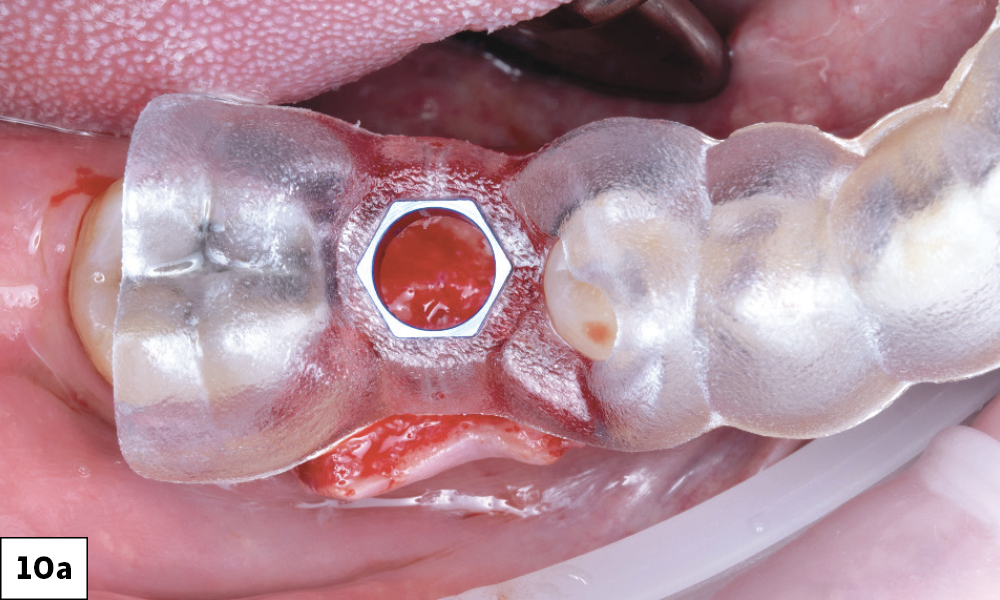

Ensuring the Tissue Flap's Non-Impedance of the Surgical Guide

Insertion of 5 x 11.55mm Glidewell HT Implant

Completed Osteotomy and Fully Visible Through Surgical Guide

Figures 10a–10c: I made sure the reflected tissue flap did not impede the seating of the guide. In this case, I could see the guide was holding the tissue out of the way on the buccal, and I was able to fully see the ridge through the access hole. Using the Glidewell HT Implant Guided Surgical Kit, I started the osteotomy with the 4.3/5.0 mm alignment drill. This drill perforates the alveolar crest and helps to establish a purchase point for all remaining drills in the sequence. The A and B pilot drills helped to provide an osteotomy depth of 8 mm and 10 mm respectively. I then moved on to using the shaping drills. I started with an 8 mm to help begin to widen the osteotomy, followed by the 11.5 mm, to fully widen the osteotomy to the proper size for the implant. The osteotomy was completed and fully visible through the guide.